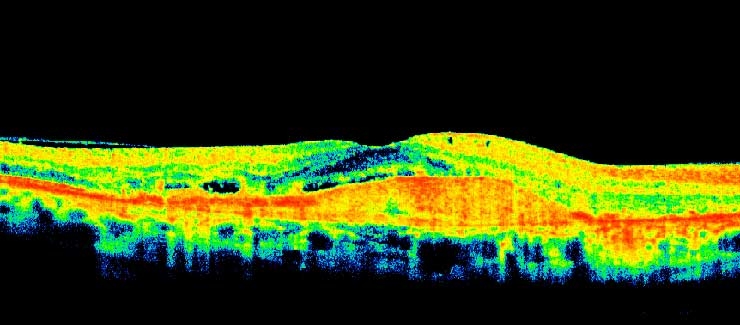

Cystoid Macular Oedema (CMO) and Pigment Epithelial Detachment

cmoped1

cmoped2